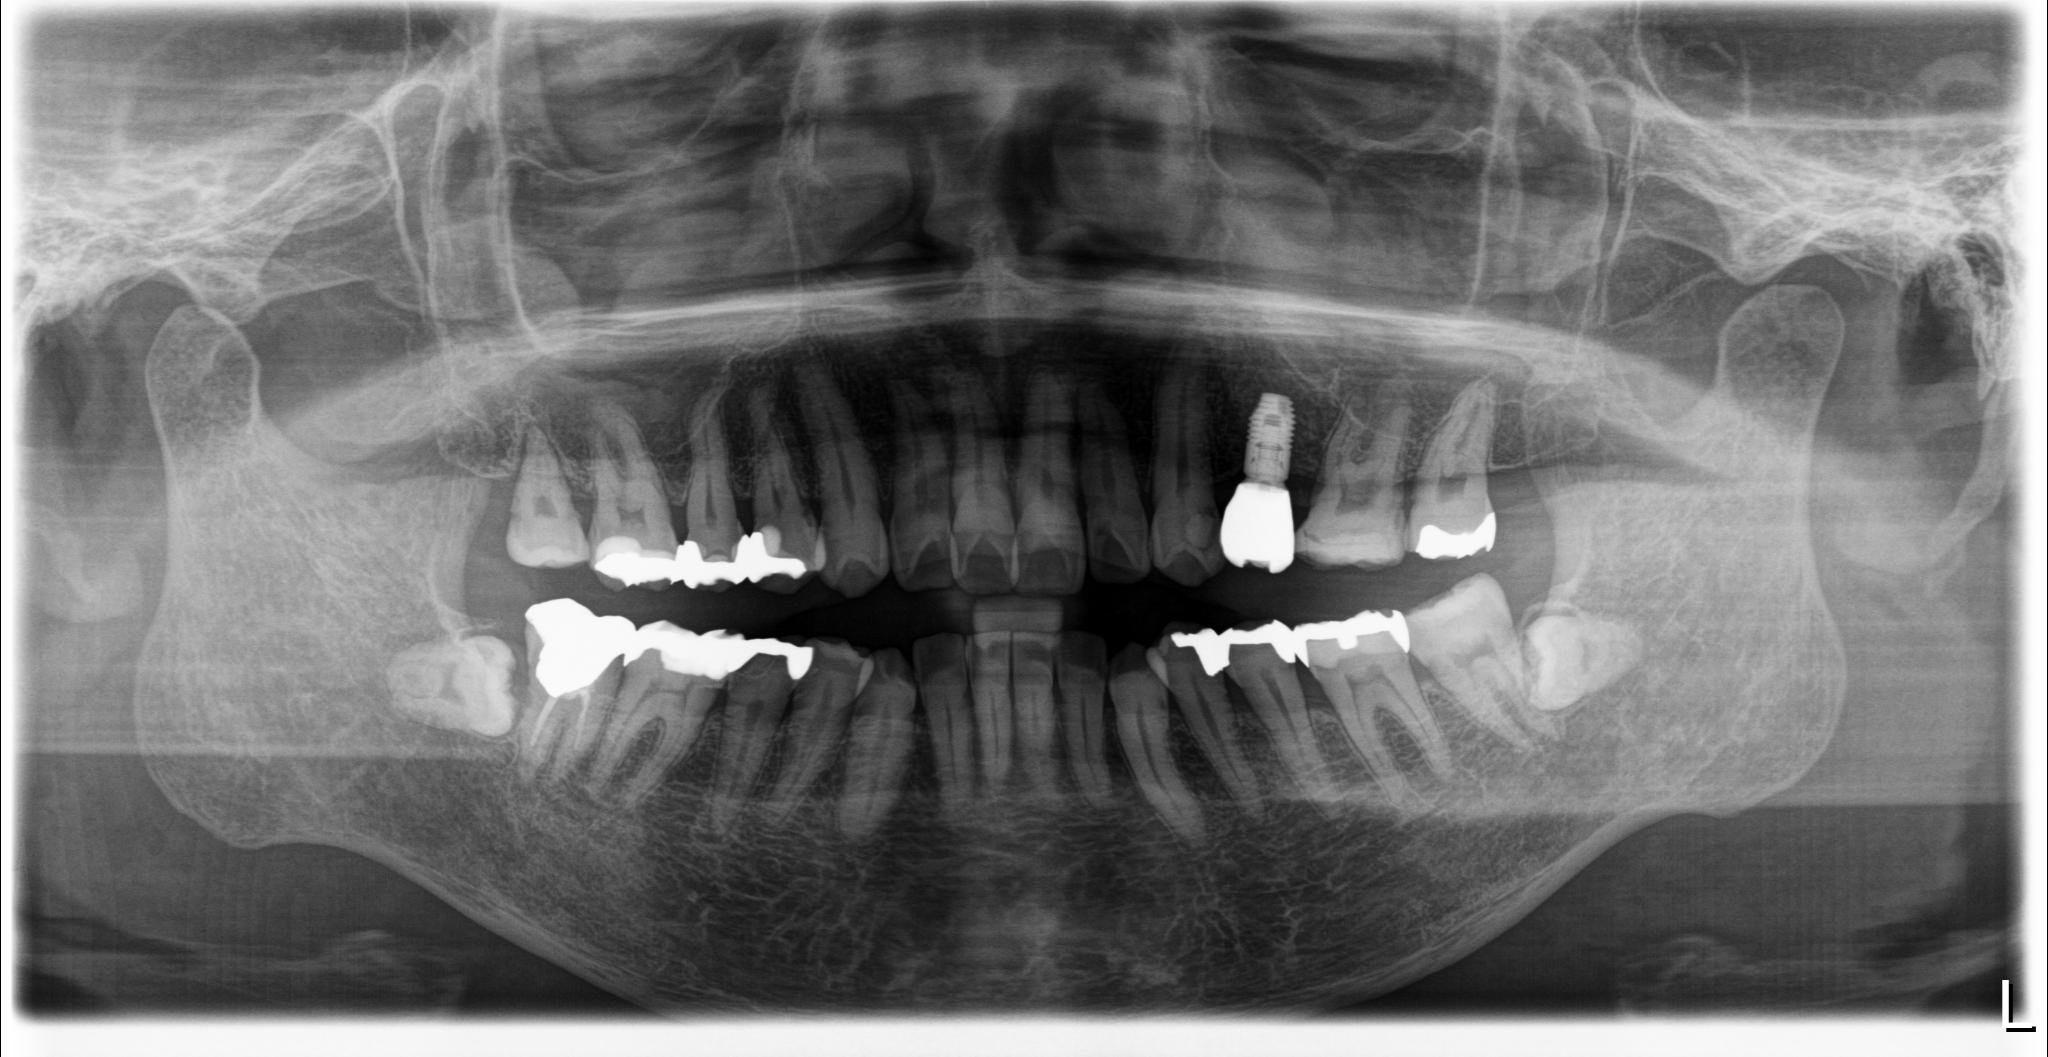

治療前レントゲン画像

治療後レントゲン画像